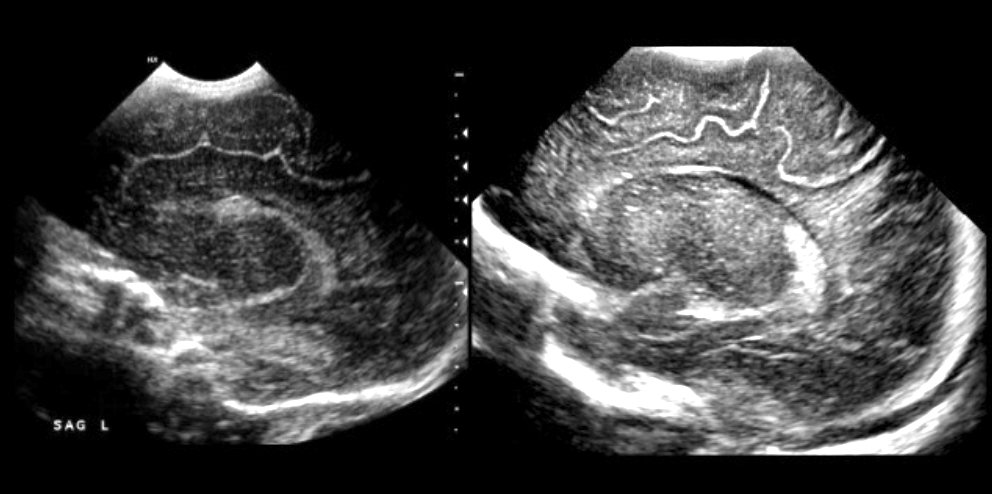

Much of my professional life has been imaging children with X-rays, ultrasound, nuclear imaging, CT, and MRI. I am intrigued by Nouwen’s insight that the Incarnation is a reimaging or a reimagining of God. Reimaging in radiology usually means taking a second look. We make another image if we are not entirely sure of what we saw the first time. When we see something we cannot quite understand, we produce another image to see if it is still there. We want to verify that what we saw the first time was real, so we take another picture, sometimes at a different angle.